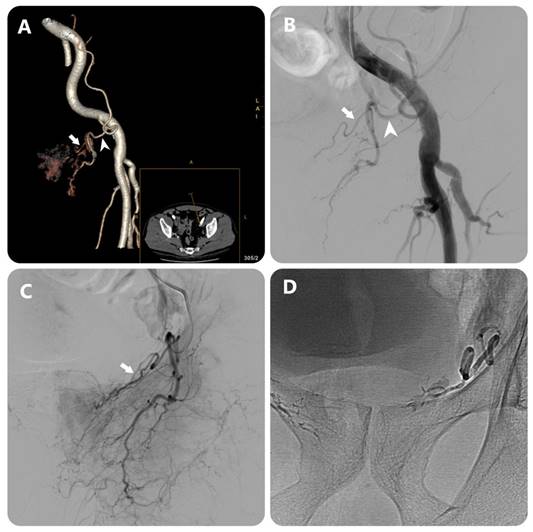

Figure 3

Images in an 80-year-old man with symptomatic BPH (prostate volume 94 mL). (a) 3D image of the left external iliac artery (EIA) and its branches from DECT data in a 15° contralateral anterior oblique direction shows left PA (white arrow) arising from accessory obturator artery (OA)(white arrowhead) (b) EIA angiography performed with injection of 12 mL of contrast medium at a rate of 6 mL/sec (3 frames per second) (c) OA angiography performed with injection of 7 mL of contrast medium at a rate of 3 mL/sec (3 frames per second) (c) Post-embolization single-shot image.

Evaluation of the group 2 in the study included 50 patients who received DECT scans before embolization to treat BPH. The results showed that the ability to detect PA on DECT was almost equivalent to DSA with a detection rate of 96.15%, no false positives, false negative rate of 3.85%. The study of Maclean et al. [18] evaluated the value of CTA in identifying the PA and the anastomoses, showing that the detection rate of the PA was 97.3%, equivalent to the results of our study. Author Kim et al. [4] evaluated the effectiveness of MRA in determining the origin of the PA before the intervention, the results showed that 26/34 PAs were identified (accounting for 76.5%) in 17 patients. In addition, in our study, the PA originating from the common trunk with superior vesical artery accounted for the highest proportion (33.2%), and the PA originating from the obturator artery was the second most common. Research by author Nguyen Xuan Hien[16] showed similar results, the most common location was from the common trunk with superior vesical artery (33.1%) and the second most common location was from the internal pudendal artery. On DECT images, determining the origin of the PA is based on the image of the artery's path from the glandular parenchyma towards the origin, due to the ability to construct MIP and 3D images and locate points on planes (Fig. 2) (Fig. 3). In addition, less common locations of origin of the PAs are the superior gluteal artery (SGA), inferior mesenteric artery (IMA), middle rectal artery, accessory internal pudendal artery (IPA), accessory obturator artery (OA), or others. In our study, the rate of rare locations (type V) was 6%, equivalent to FC Carnervale's classification [6]. In cases where the PA cannot be found when selecting the arterial branches internal iliac, especially when the ipsilateral obturator artery is not observed, then angiography of the external iliac artery should be performed to find the PA separating from the accessory obturator artery (OA) (Fig. 3). In this case, the interventionist should not let the embolization material reflux out of the PA because there is a lower limb artery occlusion risk. In addition, the PA variant originating from the accessory pudendal artery is considered the most important variant in the type V variant group because the accessory pudendal artery often has a parallel path and connects with the internal pudendal artery, so it is often very short and prone to reflux when injecting paralysis material. To avoid non-target embolization in the penile area, it is necessary to use a coil or sponge to block this connection [19]. Our study encountered 03 cases of PA originating from the accessory pudendal artery with a rate of 0.8%. DECT imaging to evaluate the PA before intervention will be helpful in pre-identifying these rare cases, helping to reduce the time to select the PA. In addition, our study also found that there was asymmetry in the origin of the pelvic artery on both sides of the pelvis in the same patient in 74.3%, similar to the study of author Wang [11]. This suggests that each side of the pelvis should be considered independent when selective arterial catheterization and embolization are performed.